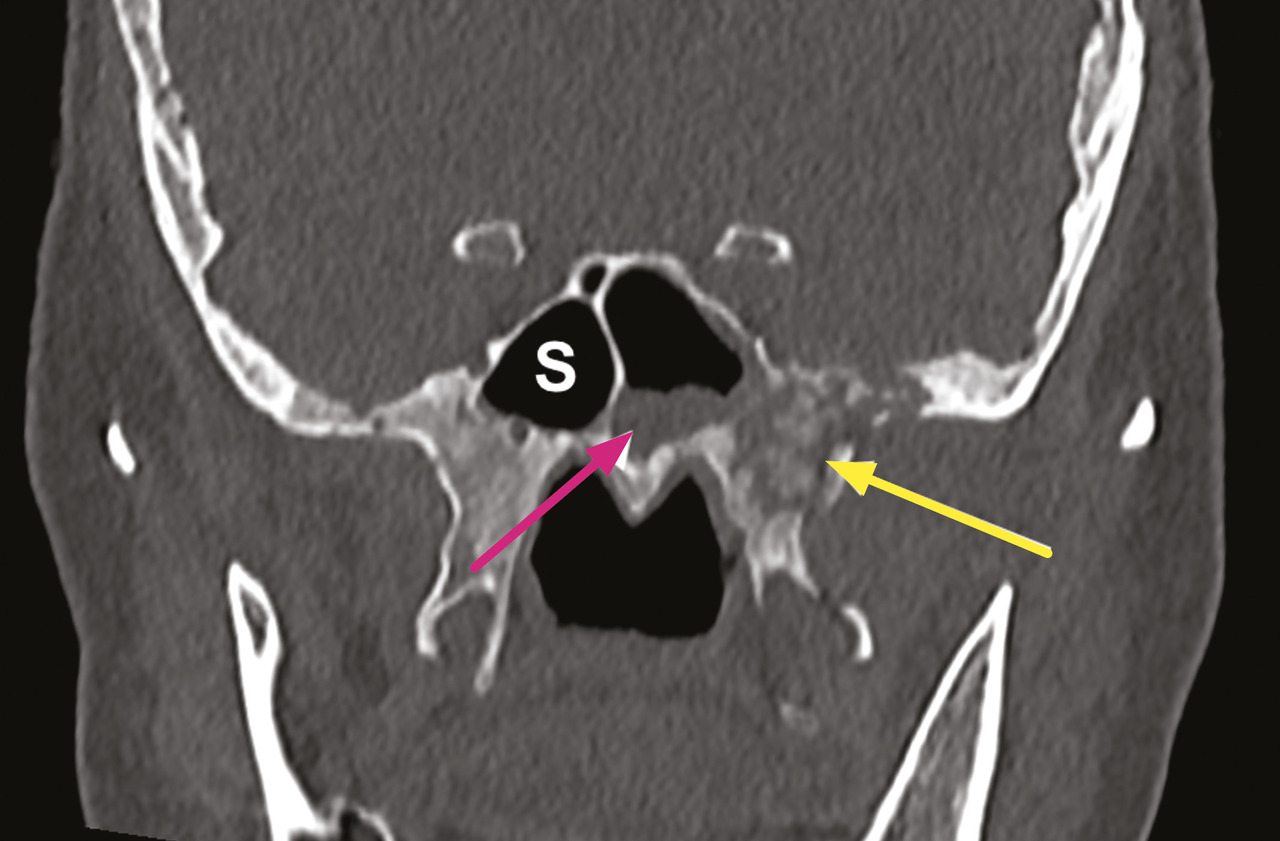

Le diagnostic d’aspergillose pulmonaire doit également faire pratiquer une imagerie sinusienne dans le bilan d’extension. L’examen d’imagerie de première intention est le scanner, qui met en évidence un épaississement muqueux sinusien associé à une ostéolyse de contact (fig. 1), qui peut cependant être inconstante dans les stades précoces de la maladie.

Le bilan comprend une imagerie par résonance magnétique (IRM) pour l’évaluation des tissus mous et une angio-tomodensitométrie (angio-TDM) pour rechercher une atteinte vasculaire. L’évolution de l’infection est en effet marquée par un angiotropisme. L’envahissement du sinus caverneux est une complication fréquente qui peut aboutir à un anévrisme mycotique de la carotide interne. L’envahissement de l’artère sphénopalatine peut entraîner l’invasion de la fosse infratemporale. L’extension depuis l’ethmoïde peut se faire vers l’orbite – induisant baisse d’acuité visuelle, ophtalmoplégie et exophtalmie – et/ou vers le compartiment intra-crânien (fig. 2).